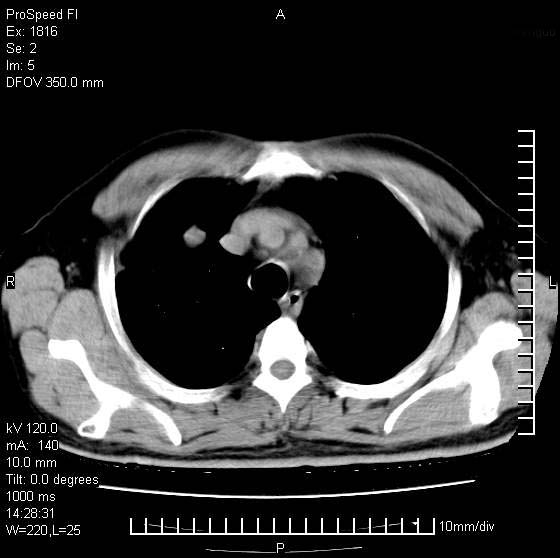

男性,50 ,肺结核9年,咳嗽,胸痛一周。右上肺见一厚壁空洞,周边有点样钙化,胸膜牵拉,洞壁较光整。诊断结核性空洞。有癌性的可能吗? 余肺野无异常,没有上传。

洞壁较厚内壁比较光整,两个病灶有关联性,纵隔淋巴结不大,考虑结核性空洞。